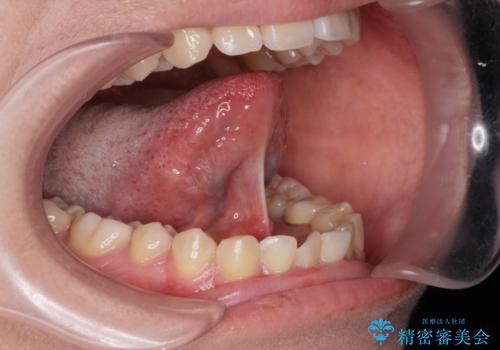

- 舌が動かしにくいとの事で来院。

舌の可動範囲が広がり満足していただけました。